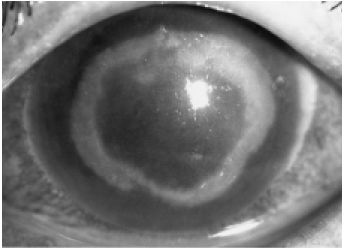

アカントアメーバ角膜炎

眼の痛みが強いのが特徴で、涙もたくさん出ます。また、白眼の充血も非常に強くなります。初期の視力低下は軽度ですが、徐々に見えにくくなり、進行すると重度の視力障害になります。目やには軽度で、通常 片眼のみに起こる片眼性に疾患です。ほとんどの場合、片方の目だけに起こります。

角膜の悪くなっている部分をこすり取って、アカントアメーバを検出します。特殊な病原体で、めずらしい病気であるため、大きな総合病院でも検査が困難なことが多いと言われています。

アメーバに対する特効薬がないため、抗真菌薬を使用しますが、それに加えて感染した角膜表面を何度も削る治療を併用する必要があります。根治には何カ月もかかることがまれではありません。どうしても治らない場合は、角膜移植を余儀なくされる場合もあります。